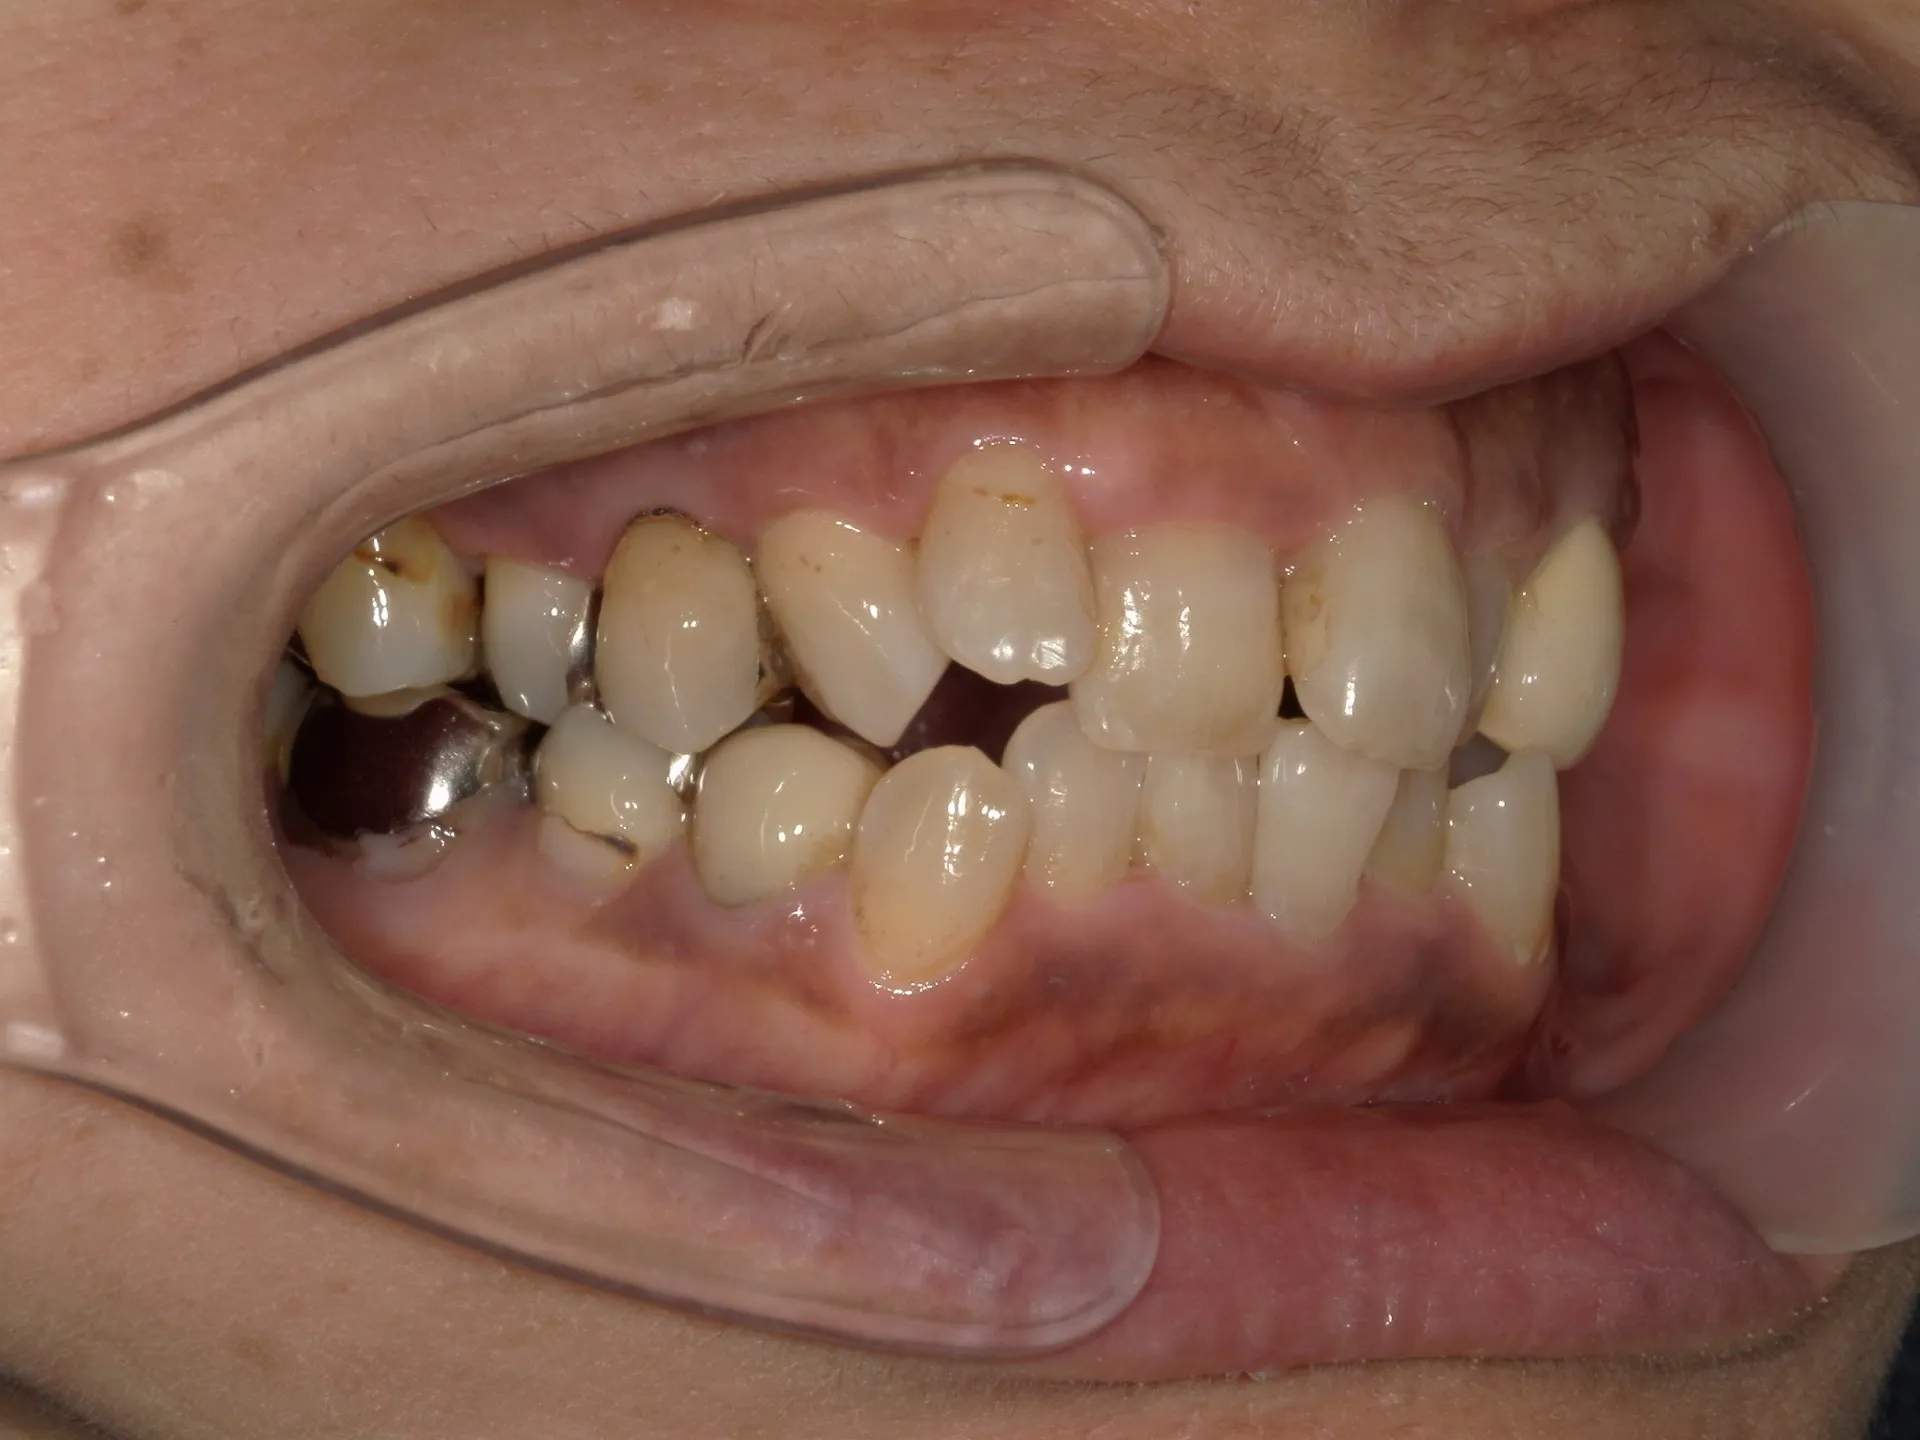

今回は65歳以上でも矯正治療を開始した症例についてご紹介いたします。

しかし、年齢がたとえ定年を迎えたあとであっても十分に矯正が行えて、今後の歯磨きが容易になり、虫歯や歯周病のリスクが減らせて歯を残すことが出来たり、歯並びが良くなったことでモチベーションも上がるなどの矯正後のメリットも非常に高いため、健康的な生活を行う上でも矯正治療は行うことをお勧めします。